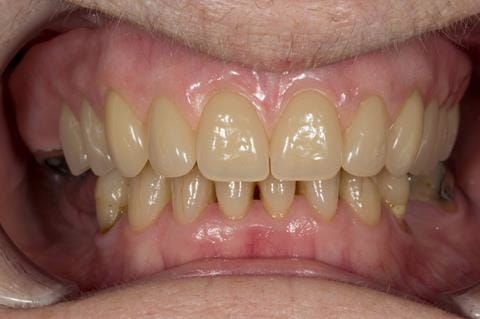

Following consultation and second discussion appointment the patient chose to have option 2 namely, a window denture - maxillary cobalt chromium based partial denture. The clinical situation and treatment process is shown in detail below with photographs. The patient was successfully rehabilitated with this and her quality of life considerably improved. The clinical work was provided by Finlay and the technical work by Rowan.